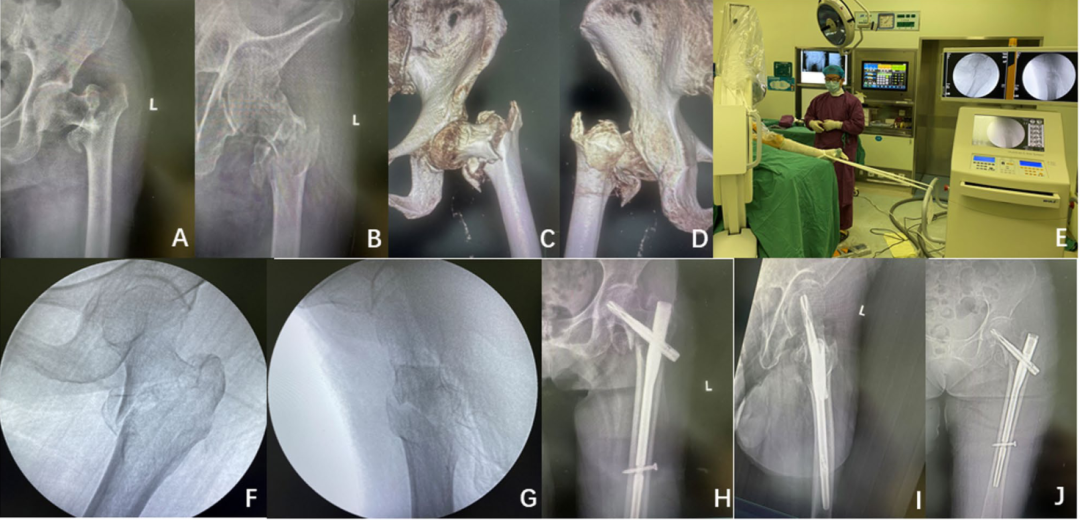

股骨转子间骨折在老年髋部骨折患者中很常见。合并症较少的患者应尽早手术。最佳治疗方案仍为微创固定和术后早期活动,虽然通过间接复位的头髓内钉仍然是金标准,如果没有牵引床,是否能完成手术。我国中南湘雅三医院骨科的医生开发了C-Flex牵引,通过C臂锚定牵引实现骨折复位和髓内固定:

(B-C) C-Flex牵引装置:患者仰卧,10 °- 15° Trendelenburg倾斜,同侧髋关节抬高,踝关节固定在C形臂机器上;

(D-E)一个由外科医生控制的复位操作是在手术过程中在荧光镜的引导下从纵向牵引开始,并通过固定C形臂的四轮制动器来保持牵引。

(B-K)四股绷带将脚踝固定在C型臂监视器把手上